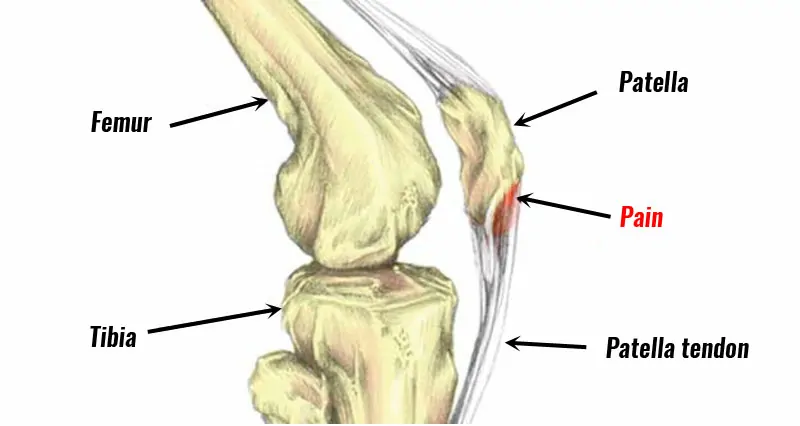

6. “Jumper’s Knee”

- What it is: Also known as patellar tendinopathy, this is an irritation of the tendon that connects the quadriceps muscle to the lower leg.

- Common Symptoms: Pain inferior to your knee cap, especially with jumping (as the name suggests!) but also with other squatting movements (ie. a plié!)

- Treatment: Relative rest (modifying your practices) is required including limiting jumping and explosive movements. Then you can start strengthening your quadricep muscle which helps to strengthen your patellar tendon. You can also get a Jumper’s Knee brace that can help decrease your symptoms during your practices.

- Prevention Tips: Keep your hip and knee muscles strong and flexible. Take special care during growth spurts when you’re young – these are the times where activity that has previously been fine can be become problematic.